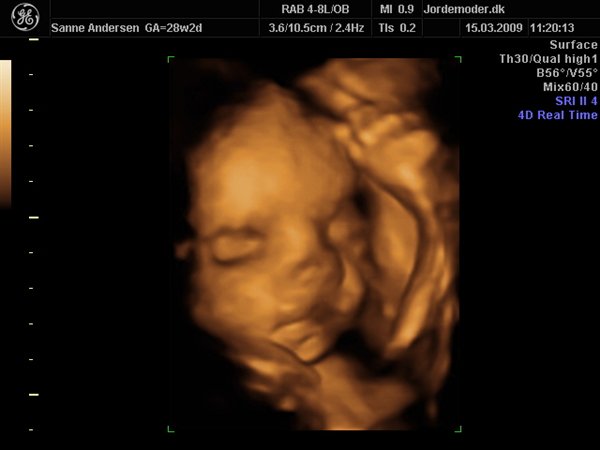

Det gik bare så godt til scanningen, men den ville meget heller sove end være aktiv så vi kunne få en masse forskellige billeder... men vi har fået en masse dejlige billeder og en dvd hvor der er masser af hjertelyd og rigtig pænt billede af hvordan hjertet slår

men vi venter en lille dreng, vi kunne desværre ikke få billede i 3d da han bare ikke ville rykke på sig og han lå så der var for meget fostervand...

Vedhæftede fotos (klik for at se i fuld størrelse)

tak.. ja det var helt fantastisk... efter lidt forvirring da de igen ikke kunne finde mig i deres system men så blev vi sendt ud til helseklinikken "jordemoder.dk" og fik lavet scanningen...